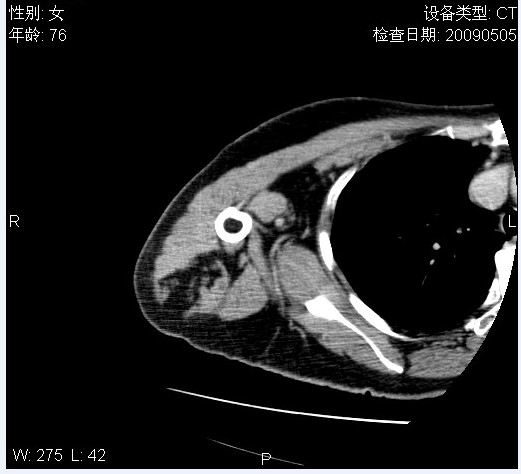

标题: CT19811:女,76岁,右上臂肿物1个月 [打印本页]

标题: CT19811:女,76岁,右上臂肿物1个月

使用了造影剂,可惜效果不太好

右肱骨上段软组织内见梭形低密度影,边界清楚,最长径约54mm.

病理结果:脂肪瘤。术中见肱骨骨膜受侵,有出血,量不详。

当时诊断意见:右肩三角肌内蔓状血管瘤(先天性动静脉瘘)。

本人对病理结果有个疑问:单纯的脂肪瘤内为什么有条状软组织影,那应该脂肪肉瘤才对啊?

该病例增强效果欠佳,由于经验欠缺,我们注射对比剂是由下肢足背静脉给药。注速2.0。虽然如此,但我们可以看到肿块内部条状软组织影是强化的,而且是连续的,并可见供血动脉是由腋动脉的其中一支即肩胛下动脉分出。从这些征象我们可以得出诊断:蔓状务血管瘤。

可病理偏偏为脂肪瘤,我怀疑取材有问题。因为蔓状血管瘤异常扩张的静脉外周是脂肪成分,它可以侵犯肌组织及骨骼。当取材于外周,那当然是脂肪瘤。此时我认为临床的最终诊断不应单从病理出发,应该综合考虑。